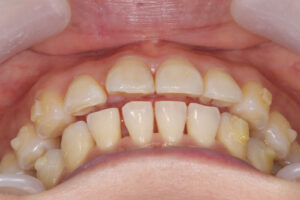

Invisalign failed orthodontic treatment

前歯が噛んでいない

Invisalign failed

奥歯が噛んでいない

Invisalign correction failure

orthodontic treatment